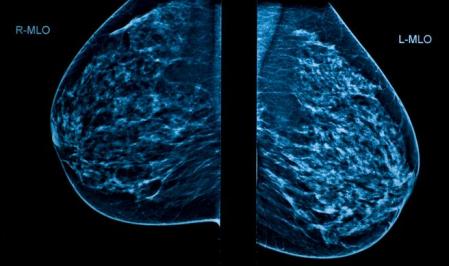

EUROPA DONNA, la Coalición Europea contra el Cáncer de Mama, remarca en este sentido que el cribado mamográfico contribuye a la detección precoz del cáncer de mama y permite detectar un cáncer incluso “tres o cuatro años antes de que una mujer descubra por ella misma los síntomas” y le permite beneficiarse de un tratamiento más temprano y menos invasivo.

“Los estudios han demostrado que la mortalidad por cáncer de mama se reduce en un 35% en las mujeres de 50 a 69 años de edad, que participan en un cribado para el cáncer de mama”, celebra. Así, la ‘reina’ de las pruebas para el cribado en el cáncer de mama es la mamografía. La Sociedad Española de Ginecología y Obstetricia (SEGO) precisa que los controles periódicos mamográficos en mujeres sin un riesgo específico para esta neoplasia suelen empezarse a la edad en la que es más frecuente la patología, en torno a los 45 años, y se mantienen hasta edades avanzadas.

Resultados de una mamografía

Mamografías: Imágenes de rayos X que detectan zonas anómalas en la mama. No tienen un 100% de fiabilidad por lo que pueden dar imágenes sospechosas que finalmente no sean malignas (falsos positivos) o dejar de diagnosticar algún tumor maligno (falsos negativos).